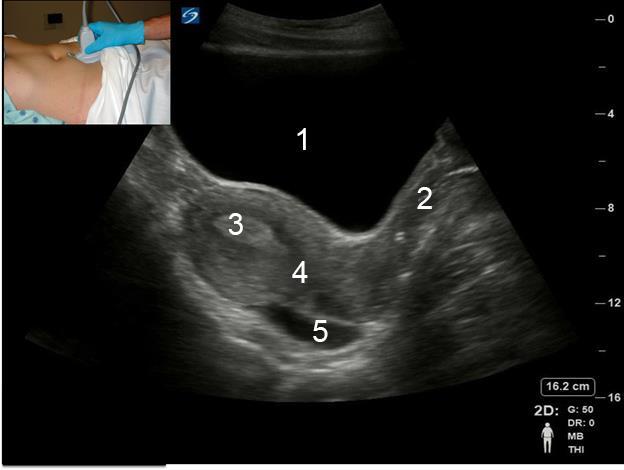

Pelvic Transabdominal (TA) Scanning – Sagittal Image

1. Bladder

2. Vagina

3. Endometrium

4. Uterus

5. Posterior Cul-de-sac